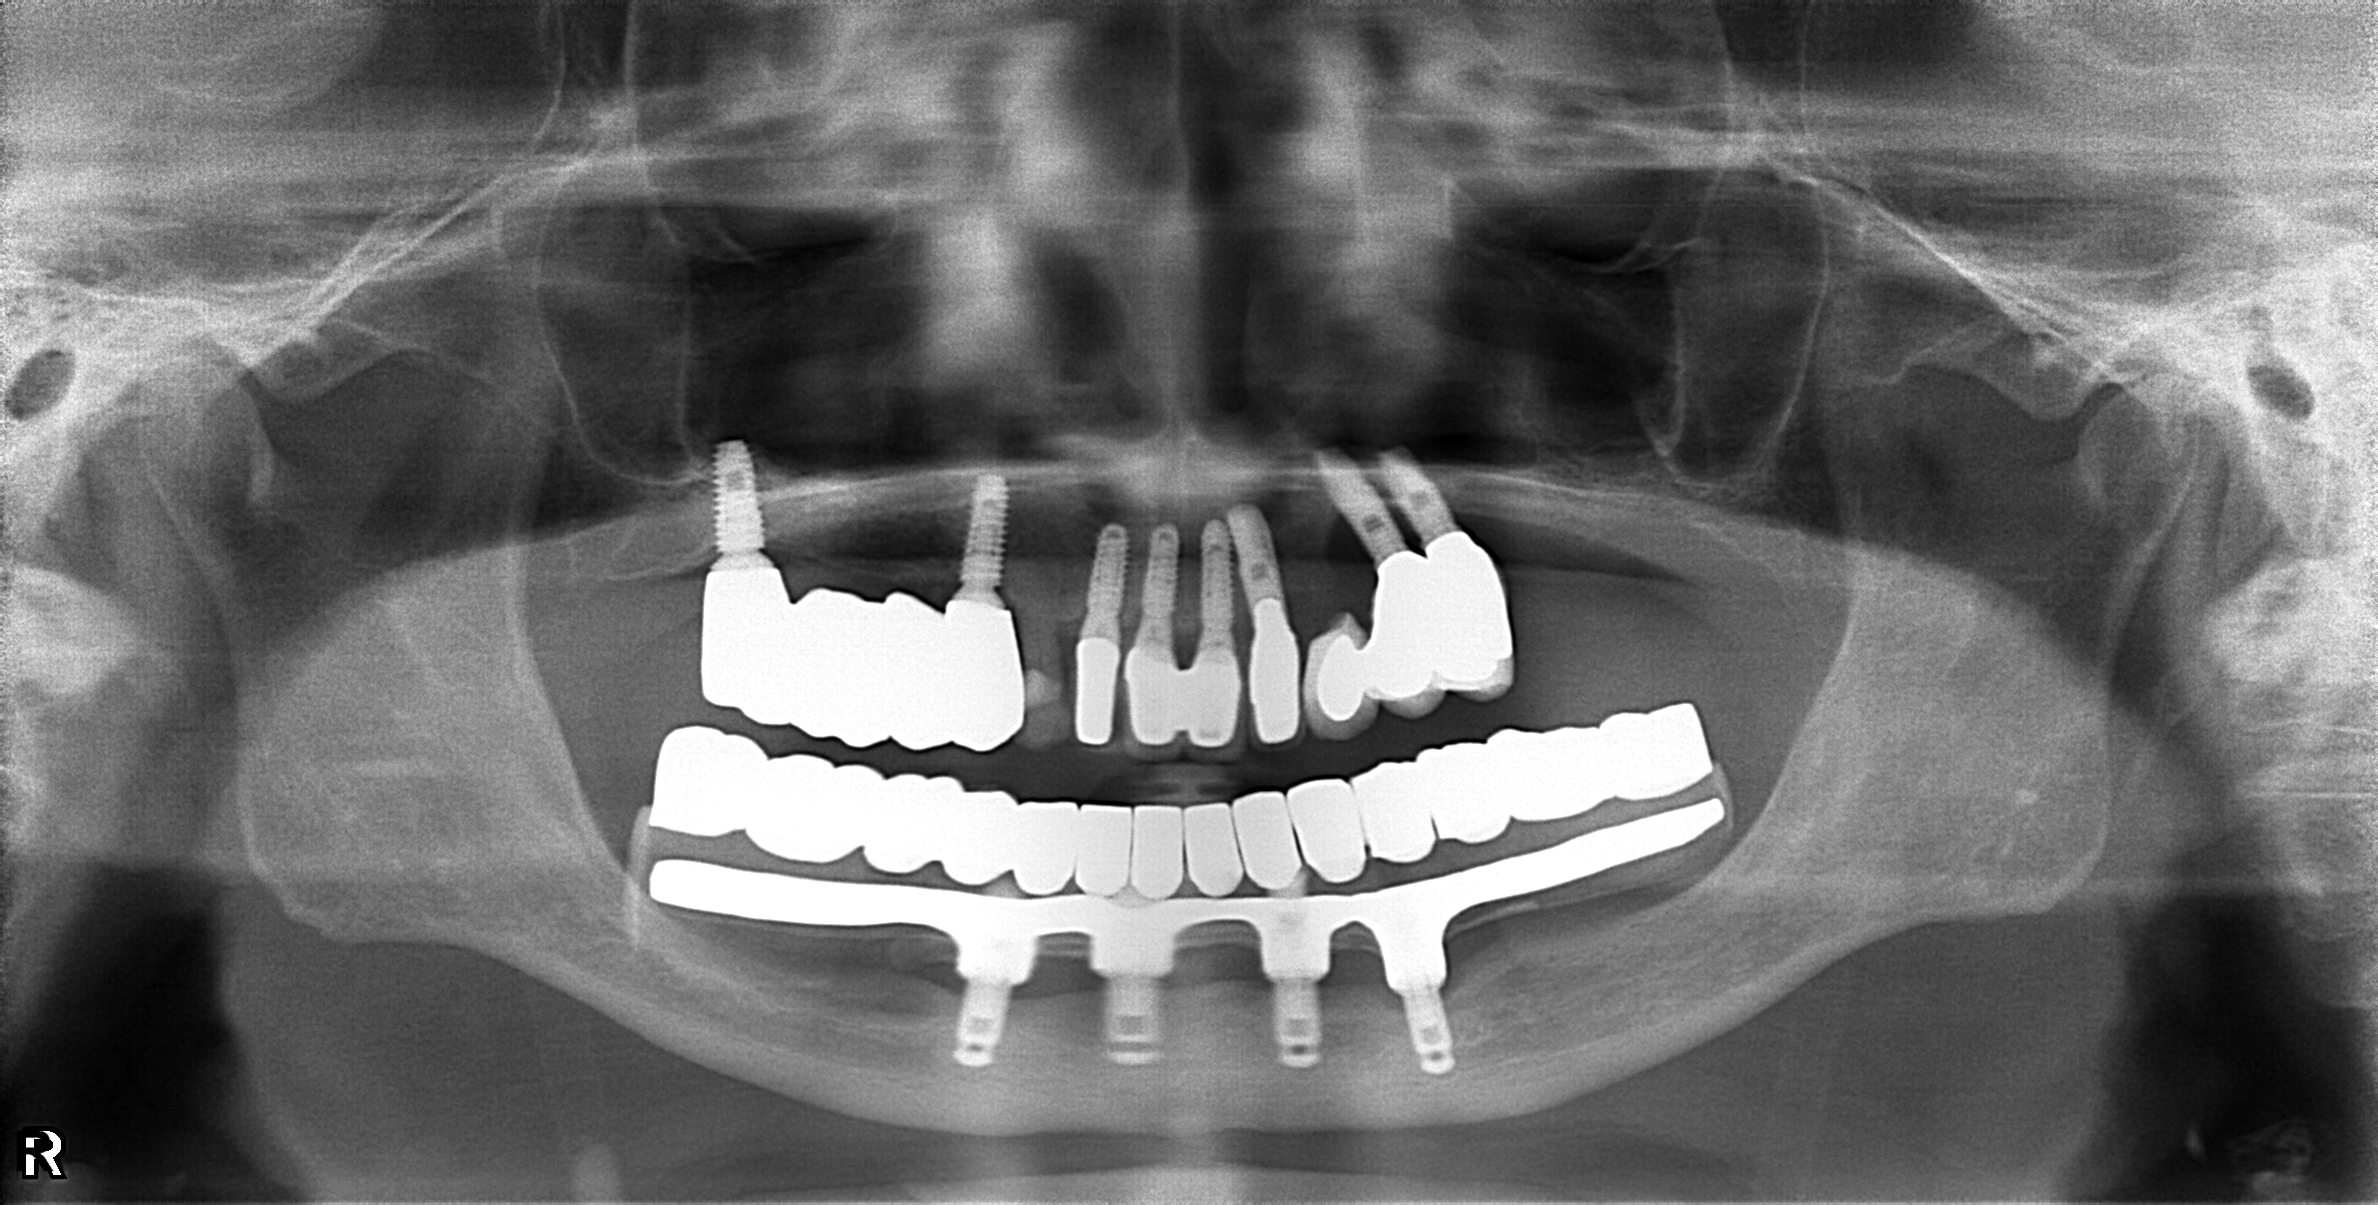

案例二-下顎

醫生透過電腦斷層及全口X光照片評估骨頭狀況決定植入的植體數量、寬度以及深度

大約3-4的癒合時間,把臨時假牙取下並鎖上正式假牙

完成!